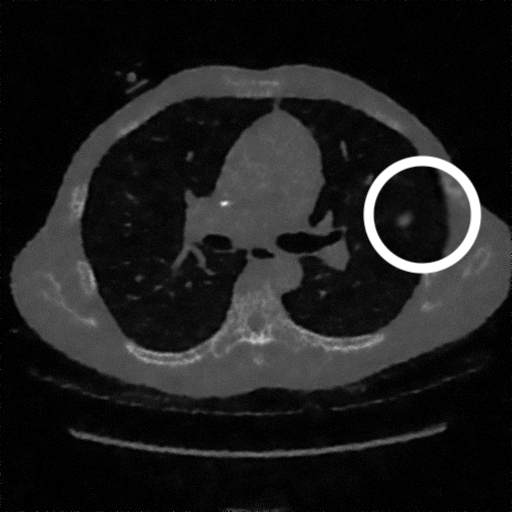

3.1.3 Example 2: data driven reconstruction methods in lung CT screening

There is sufficient evidence that screening for certain tumours using CT images may improve prognosis of cancer survivability (citep \@BBN(Boiselle, 2013)). As mentioned above, in order to gain better image quality with less X-ray dose, many enhanced regularization techniques with integrated machine learning steps have been suggested for CT reconstruction, and in a full reference setting they are commonly evaluated by applying PSNR and SSIM, see e.g. (citep \@BBN(Adler and Öktem, 2018; Hendriksen, Pelt, and Batenburg, 2020; Unal, Ertas, and Yildirim, 2021)). As CT images are generally taken to perform a clinical task, they are not the final step of a medical process but often the initial one. Therefore the definition of what makes a good image heavily depends on the task in hand, and for prognosis related cancer the identification of tumours is of upmost importance.

In on-going research on photon counting detector types and screening procedures for lung cancer (EPSCR grant: EP/W004445/1) an experiment was conducted testing enhanced reconstruction algorithms. Simulations using less than 10% of a clinical X-ray dose were performed to investigate if data-driven methods could sufficiently enhance the images to clearly see the tumours in the lungs while providing very low amount of dosage to the patients. The corresponding data was a CT-dose simulation, using images from the open LIDC-IDRI dataset (citep \@BBN(Armato et al., 2011)) as references, as well as simulated and reconstructed images with in-house software. Figure 3 shows the results of the experiment. We show the reference image used as basis for the simulation, together with five different reconstruction algorithms. The first is an iterative solver, a gradient descend algorithm with TV minimization (citep \@BBN(Sidky et al., 2012)) and (c)-(f) correspond to machine learning methods: FBPConvnet is a denoising algorithm that cleans the bad image (citep \@BBN(Jin et al., 2017)), LPD is an iterative unrolled method that combines traditional solvers with machine learning (citep \@BBN(Adler and Öktem, 2018)), Noise2Inverse is a self-supervised learning method (i.e. does not require ground truth data) (citep \@BBN(Hendriksen et al., 2020)) and ItNet is another iterative unrolled method, the best performing winner of the AAPM DL-Sparse-View CT challenge (citep \@BBN(Genzel, Macdonald, and März, 2021)). ItNet is also judged here as the best result according to PSNR, SSIM and LPIPS.

Refer to caption

(a) Reference

(b) (27.6, 0.70, 0.37)

(c) (31.9, 0.73, 0.29)

(d) (32.5, 0.84, 0.19)

(e) (32.5,0.77, 0.20)

(f) (33.0, 0.89, 0.12)

Figure 3: Reference image (a) and outputs of different reconstruction methods (b)-(f) applied to dose simulated data. PSNR/SSIM/LPIPS are unable to identify the best reconstruction (c), where also the tumour is visualized well.

FR-IQA mismatches

This experiment was performed to evaluate the quality of different kinds of CT reconstruction, and especially the lung tumour detection capabilities thereof. The best result according to the chosen IQA measures is given by ItNet in Figure 3(f), which performs visually poorly. Not only the tumour (zoomed in white circle) is significantly less visible in the reconstruction, but ItNet also produces structures in the lung that are different than the ones in the reference image; it blurs and lengthens much of the soft tissue present in the lungs and it also created structure from noise in some places. Moreover, the image is overly smooth. Comparing the other reconstruction algorithms, it seems that FBPConvnet Figure 3(c) is the one performing best at preserving the shape of the lung nodule, even when the resulting image contains enhanced pixel-level noise.

We can see here that the qualitative findings strongly contradict the numbers provided by the selected measures. The reconstruction of ItNet, Figure 3(f), is outperforming the other reconstructions in regards of the measures, and the qualitative winner FBPConvnet, Figure 3(c), is judged as second worst by the same measures. This experiment suggests that the discussed measures are not a good choice for that kind of CT reconstruction applications and are yielding misleading results.

While pixel-independent random noise may be a worse effect in a natural image than a slightly oversmooth reconstruction, this is not true in CT images, where small structures may disappear if smoothing is promoted against edge preservation. In iterative reconstruction algorithms such choices are explicitly made by choosing the prior appropriately, in data-driven models the researcher has limited control on the type of implicit priors the algorithm learns from the data, i.e. model builders do not know what the algorithms chooses to learn from the ground truth. In these cases appropriate evaluation would therefore be even more important to ensure quality. If this is followed by a blind evaluation using non-appropriate metrics, the promotion of less desirable images can happen, chosen by an implicit assumption on the metric rather than the actual goal of the task.